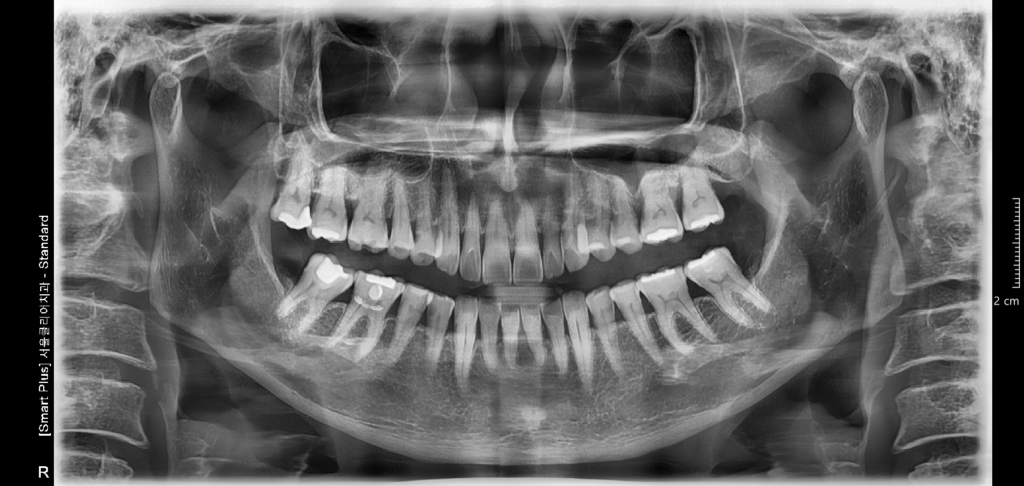

2. 방사선 사진 (파노라마 사진) 1장 & 입안 사진 촬영 및 구강스캔을 힙니다.

파노라마 사진은 입안 전체의 치아 상태를 한번에 확인 할 수 있어서 매우 유용합니다.